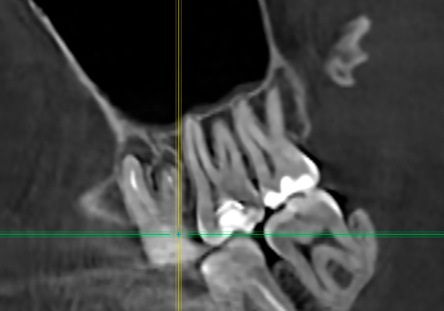

Аноним 08/08/25 Птн 06:11:54 1635233 32

1759678455236.jpg 1558Кб, 2536x3256

2536x3256

1759678455268.jpg 1853Кб, 2252x3434

2252x3434

1759678455308.jpg 217Кб, 1056x1126

1056x1126

1000076562.jpg 534Кб, 1920x1440

1920x1440

1759678455314.jpg 479Кб, 1920x1440

1759678455331.jpg 508Кб, 1920x1440

1759678455339.jpg 562Кб, 1920x1440

Насколько все плохо? Сколько готовить?

Живу в Москве, боюсь. Так что придется искать тех, кто с наркозом работает.